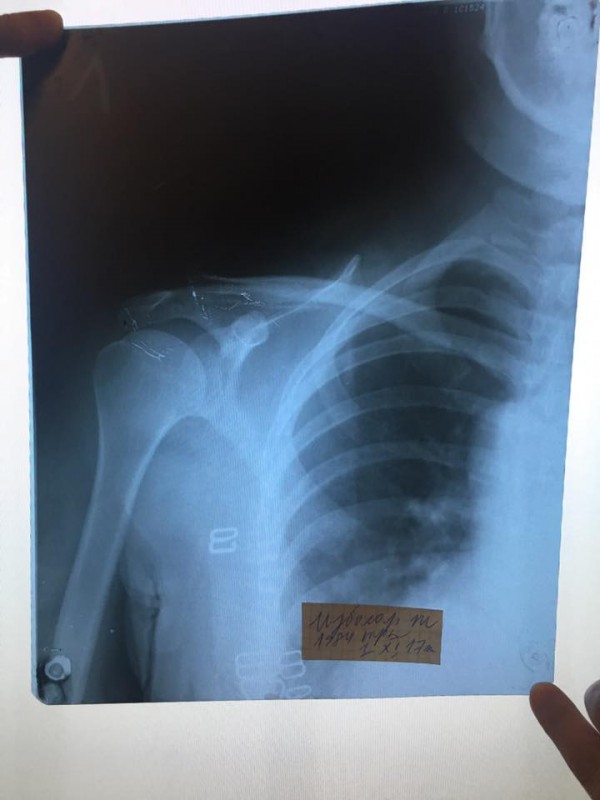

Ночью левая рука стала сильно болеть, обратилась в городскую больницу, рентген показал что у меня закрытый перелом левой ключицы, сейчас я мать четверых детей, гражданка Республики Казахстан стою перед фактом что органы и их сотрудники, которые должны защищать наши права, унизили и растоптали меня, морально и физически уничтожили, сломали мне ключицу, и скорее всего уйдут от ответственности, следователь ДГД сказал мне что решение примется через месяц, это я воспринимаю как "потянуть время", мы простые люди и не имеет высоких покровителей, надежда на общественность, которая может повлиять на этих сотрудников. Такое может произойти с каждым, помогите мне. P.S. на третьем этаже стояли несколько видеокамер, надеюсь записи дойдут до суда!!!", - написала она (пунктуация и орфография в основном сохранены - прим.).

Там же Избасар выложила фотографию заключения травматолога и рентгеновский снимок сломанной ключицы.